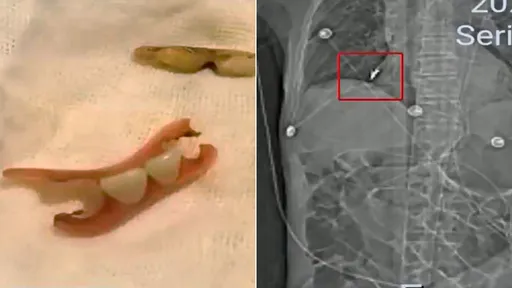

...導】中國江蘇省常州市一名85歲孫姓老翁,今年3月時胃病而住院治療,隔天手術後情況好轉,想不到之後突然...